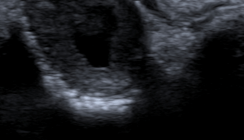

A hyperplastic dental follicle was diagnosed histologically when the soft tissue lining was composed of reduced enamel epithelium and there was an increased thickness of the follicular connective tissues, often containing numerous islands of odontogenic epithelium (Fig. 1). A cyst was diagnosed when there was metaplastic transformation of the reduced enamel epithelium of the follicle to a stratified squamous epithelium lining (Fig. 2). A chronic inflammatory cell infiltrate in the adjacent fibro-vascular connective tissues was a common finding (Fig. 3).